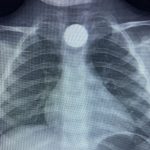

Olay, İnegöl’ün kırsal Yeniceköy Mahallesi’ndeki bir evde meydana geldi. 3 yaşındaki Bilal K., evde yerde bulduğu 50 kuruş madeni parayı ağzına atıp yuttu. Olayı fark eden ailesi tarafından çocuk özel araçla İnegöl Devlet Hastanesi’ne kaldırıldı. Yapılan tetkiklerde yemek borusunda takılı kalan madeni para görüldü. Çocuk ilk tedavinin ardından ambulansla Bursa Yüksek İhtisas Eğitim Ve Araştırma Hastanesi’ne sevk edildi.